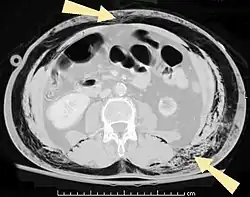

Scanner abdominal (rayons X) d'un patient présentant des emphysèmes sous-cutanés (fléchés). | |

Les cas importants d'emphysème sous-cutané sont faciles à diagnostiquer en raison des signes caractéristiques de l'affection. Dans certains cas, les signes sont subtils, ce qui rend le diagnostic plus difficile. L'imagerie médicale est utilisée pour diagnostiquer la maladie ou confirmer un diagnostic établi à l'aide de signes cliniques. Sur une radiographie du thorax, l'emphysème sous-cutané peut être vu comme des stries radiotransparentes dans le modèle attendu du groupe de muscles principaux du pectoral. L'air présent dans les tissus sous-cutanés peut interférer avec la radiographie du thorax, ce qui peut masquer des affections graves comme le pneumothorax. Elle peut également réduire l'efficacité de l'échographie thoracique. D'autre part, comme l'emphysème sous-cutané peut être visible sur les radiographies du thorax avant un pneumothorax, sa présence peut être utilisée pour déduire celle de cette dernière lésion. L'emphysème sous-cutané peut également être observé sur les scanners, les poches d'air apparaissant comme des zones sombres. Le scanner est si sensible qu'il permet généralement de trouver l'endroit exact d'où l'air pénètre dans les tissus mous. En 1994, M. T. Macklin et C. C. Macklin ont publié d'autres aperçus sur la physiopathologie du syndrome de Macklin spontané survenant à la suite d'une grave crise d'asthme. La présence d'un emphysème sous-cutané chez une personne qui semble très malade et fébrile après une crise de vomissements suivie d'une douleur thoracique gauche est très évocatrice du diagnostic du syndrome de Boerhaave, qui est une urgence vitale causée par une rupture de l'œsophage distal. L'emphysème sous-cutané peut être une complication de l'insufflation de CO2 avec la chirurgie laparoscopique. Une augmentation soudaine du CO2 en fin de marée après la hausse initiale qui se produit avec l'insufflation (les 15-30 premières minutes) devrait faire suspecter un emphysème sous-cutané. Il est à noter que l'oxymétrie de pouls et la pression des voies aériennes ne varient pas dans l'emphysème sous-cutané, contrairement à l'intubation endobronchique, au capnothorax, au pneumothorax ou à l'embolie au CO2.